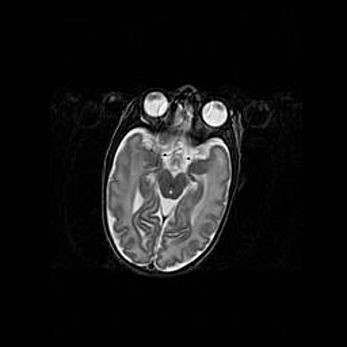

Церебральная ишемия II.

Возраст: 7 дней

Вес: 3350 г

Пол: женский

Окружность головы: 35 см

Срок гестации: 39 недель

Ишемия головного мозга – это состояние, которое развивается в ответ на кислородное голодание вследствие недостаточного мозгового кровообращения. У новорожденных она является следствием дефицита кислорода, что ведет к метаболическим расстройствам различной степени тяжести в тканях головного мозга, в том числе к развитию коагуляционных некрозов и гибели нейронов.